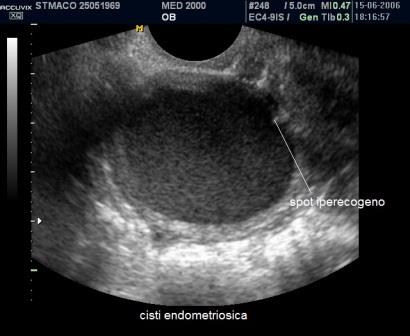

E' la localizzazione più frequente della patologia endometriosica rappresentando circa il 65% dei casi; gli aspetti ecografici più comuni delle cisti endometriosiche ovariche o endometriomi sono:

- cisti uniloculare o multiloculare con un massimo di 4 concamerazioni;

- contenuto "ground glass" ("a vetro smerigliato") legato all'accumulo di cellule ematiche che sfaldano dalla parete e di emosiderina;

- presenza di foci iperecogeni di parete;

- parete esterna della cisti spessa a superficie regolare;

- modesta vascolarizzazione di parete.